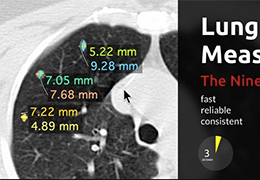

成像智能。

Eclipse 成像智能功能提供强大的处理能力和最佳质量的影像,同时减少质量错误并提高剂量效率。

凭借 AI、专有算法和先进的影像处理能力,提供出色的影像质量和无与伦比的诊断信心。

提供相配视图选项,以减少所需的曝光次数,并提供更清晰的感兴趣区域视图。